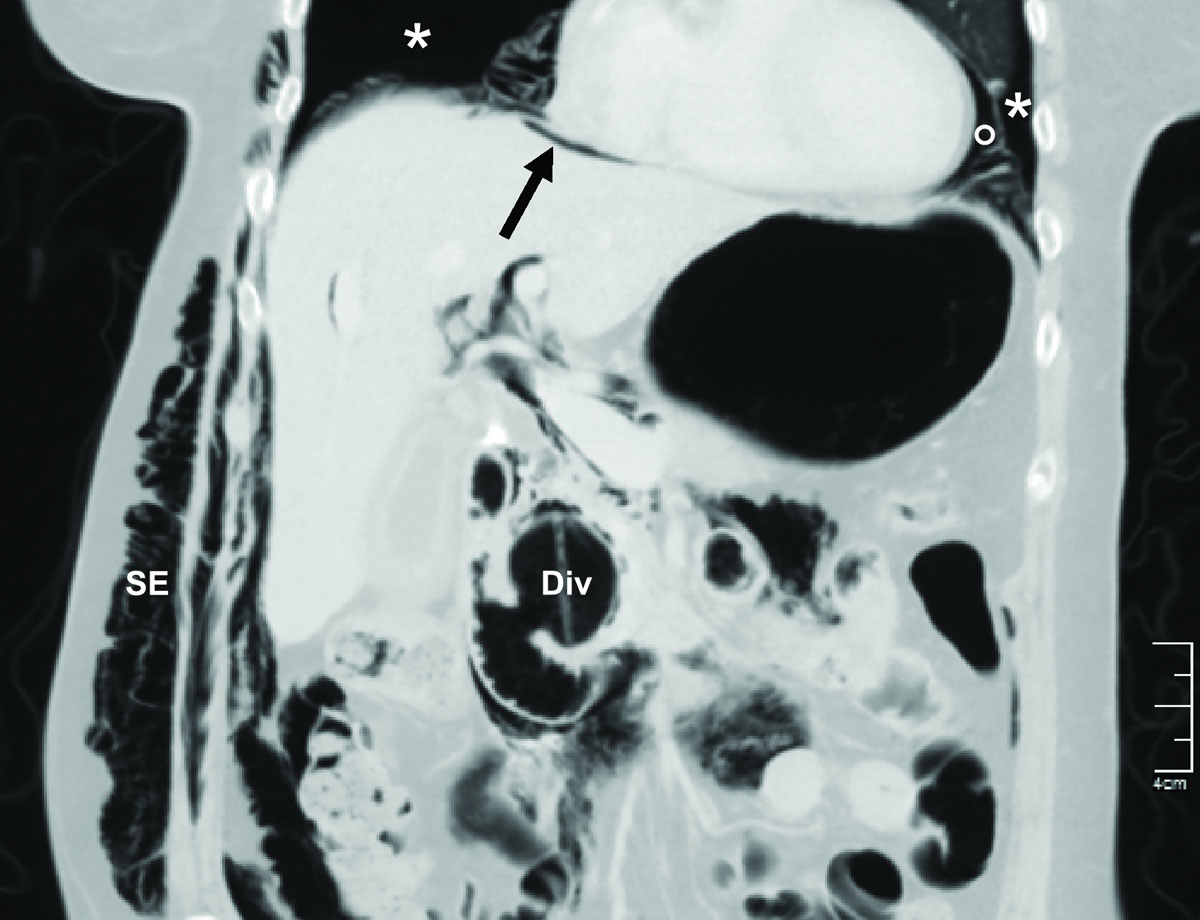

The clinical signs and diagnosis of an ERCP-related perforation have been described extensively [4, 12, 39, 58]. A thoraco-abdominal CT scan is the diagnostic gold standard for evaluating the problem (fig. 3) [59]. The classical clinical signs of small pneumothoraces, such as diminished breath sounds and tympanic percussion, are frequently overlooked, particularly in patients who are otherwise stable post-ERCP. Subcutaneous emphysema, which was often present in the reported cases (78%), is a highly suspicious sign of an air-containing organ perforation, even without pneumothorax formation. A tension pneumothorax should be suspected when patients exhibit neck vein distention, tracheal deviation, tachycardia, and/or desaturation. Moreover, decompensation signs, such as respiratory distress or circulatory instability, should rouse suspicion of a tension pneumothorax, and after clinical confirmation, it should lead to immediate decompression, without further delay, even for imaging. However, in stable patients suspected of having a perforation with pneumothorax, radiographic evaluation should be performed before drainage, as suggested by the authors of a recent review [60].

Figure 3 Post-ERCP abdominal computed tomography scan of a 75-year old patient at our institution demonstrating bilateral pneumothoraces (*), pneumomediastinum (°), pneumoperitoneum (arrow), and subcutaneous emphysema (SE). A peri-ampullary diverticulum (Div) is also present. A smaller but significant pneumothorax could have been missed, since the thorax was incompletely scanned.

A simple chest X-ray or sonography [53, 61] may exclude relevant pneumothorax formations. However, in accordance with the newest recommendations from the European Society of Gastrointestinal Endoscopy on iatrogenic endoscopic perforations [59], we strongly recommend an imaging evaluation with a thoraco-abdominal CT scan in such patients. The presence of a duodenal diverticulum, the performance of a PCP or ES and long procedure times should be considered reasons to lower the threshold for additional diagnostic studies after the intervention. In the specific case of intra-interventional suspicion of perforation and the beginning of a tension pneumothorax, the use of fluoroscopy, which is typically available in the ERCP-room, might enable an immediate diagnosis [18, 22, 31, 40]. However, minimum pneumothorax formations might be overlooked, due to the supine positioning. Finally, a loss of image resolution might be an indirect sign of extraluminal air formation. This finding should suggest the need for additional imaging studies, such as CT.